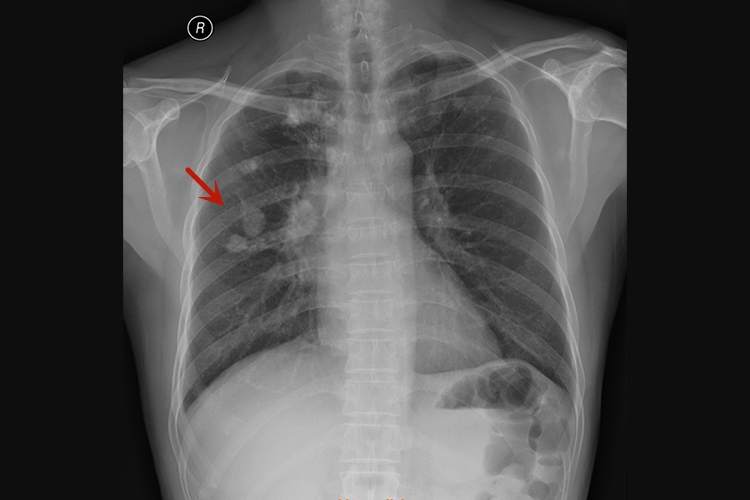

已经钙化的肺结核一般为结核球,胸X线片上常呈现境界清晰、密度较高的球形阴影,其内可有钙化,近心端有小溶解区,周围可有卫星灶及胸膜粘连,表现为斑点、条索、结节状影。